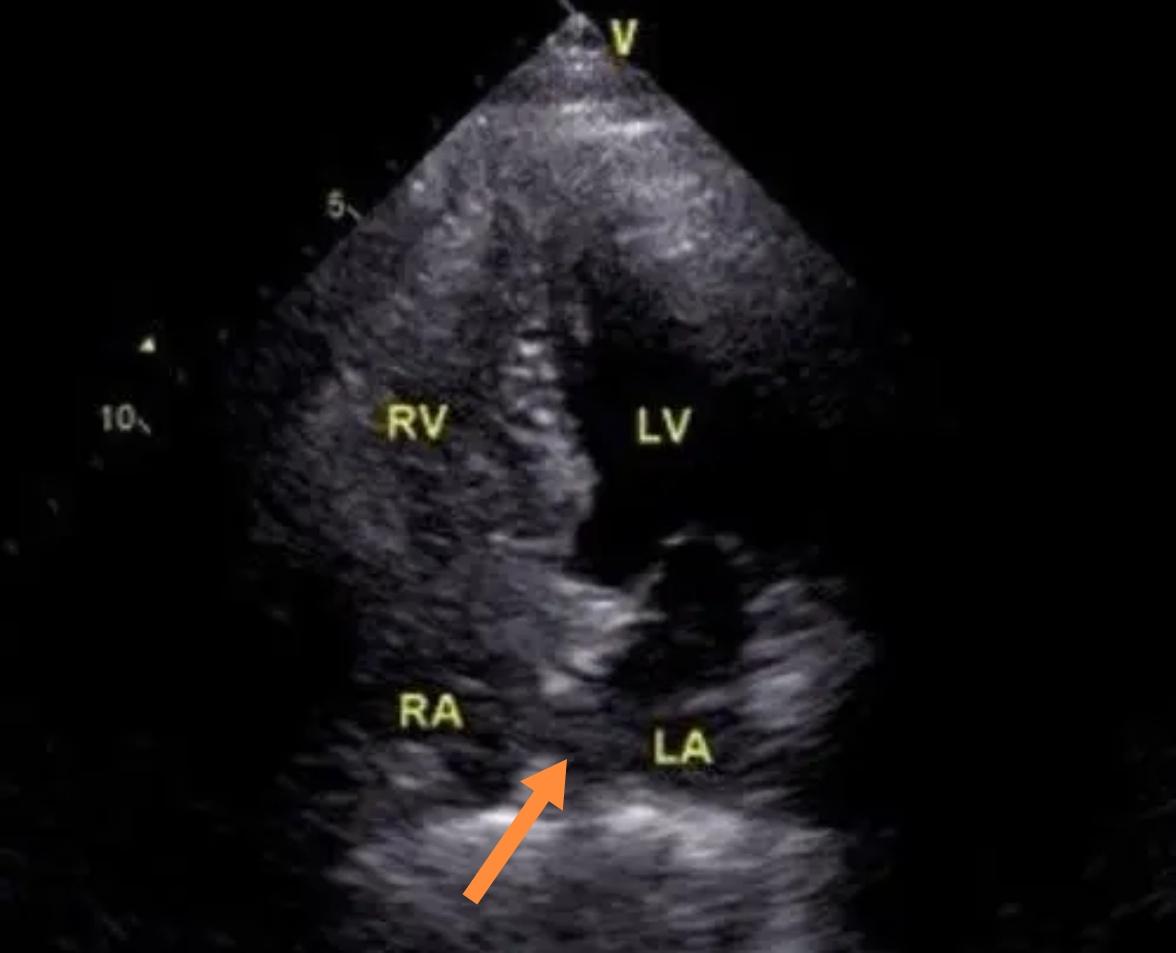

卵圆孔是胎儿发育所必需的一条生命通道,出生后大多数人原发隔、继发隔相互贴近、粘连、融合形成永久性房间隔(红色箭头所指处)。

若3岁以上卵圆孔未完全融合,遗留裂隙样通道,称为卵圆孔未闭(PFO)。

诊断依靠经胸/经食管超声心动图(白色箭头所指处),超声声学造影可发现潜在的卵圆孔未闭(黄色箭头所指处)。